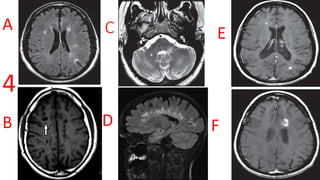

Multiple Sclerosis

• A- FLAIR best for periventricular and juxtacortical lesions.

• B- Black hole sign On MRI T1W

• C- T2 images are often best for viewing infratentorial lesions.

• D- dawsons fingers

• E- Homogenous uptake of contrast.

• F- Open-ring pattern, specific for demyelinating lesions.